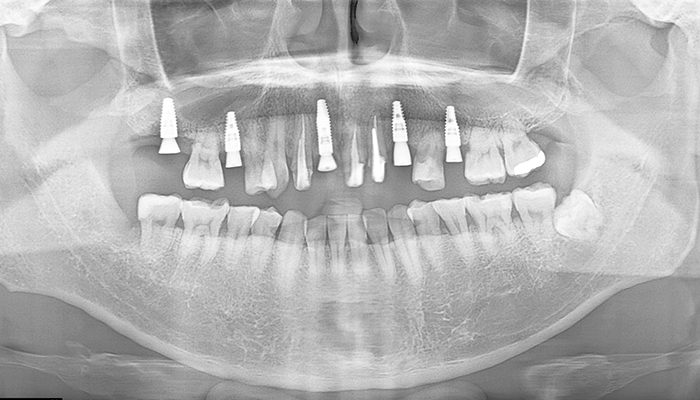

【50代男性】前歯のインプラント症例

「事故で下の歯を欠損したのを治したい」

治療前

治療後

CT画像

| 主訴 | 事故で怪我したため、欠損した箇所を治したい |

|---|---|

| 治療期間 | 約9ヶ月 |

| 治療費 | 合計1,600,000円(税別) 下の歯だけのインプラント:100万円(税別) |

| 治療内容 | 事故で骨内に入り込んだ歯を整復して、修復治療・欠損した箇所についてはインプラント治療を行いました。 ・GBRで骨造成を行い、インプラント2本を埋入し、ブリッジにて治療。 ・エクストリュージョン(歯根挺出術)。 |

| 治療のリスク | 前歯のインプラント治療では、審美性の問題や骨密度不足によるインプラントの不安定、神経損傷や感染のリスクがあり、術後の腫れや痛みも発生する可能性があります。 |